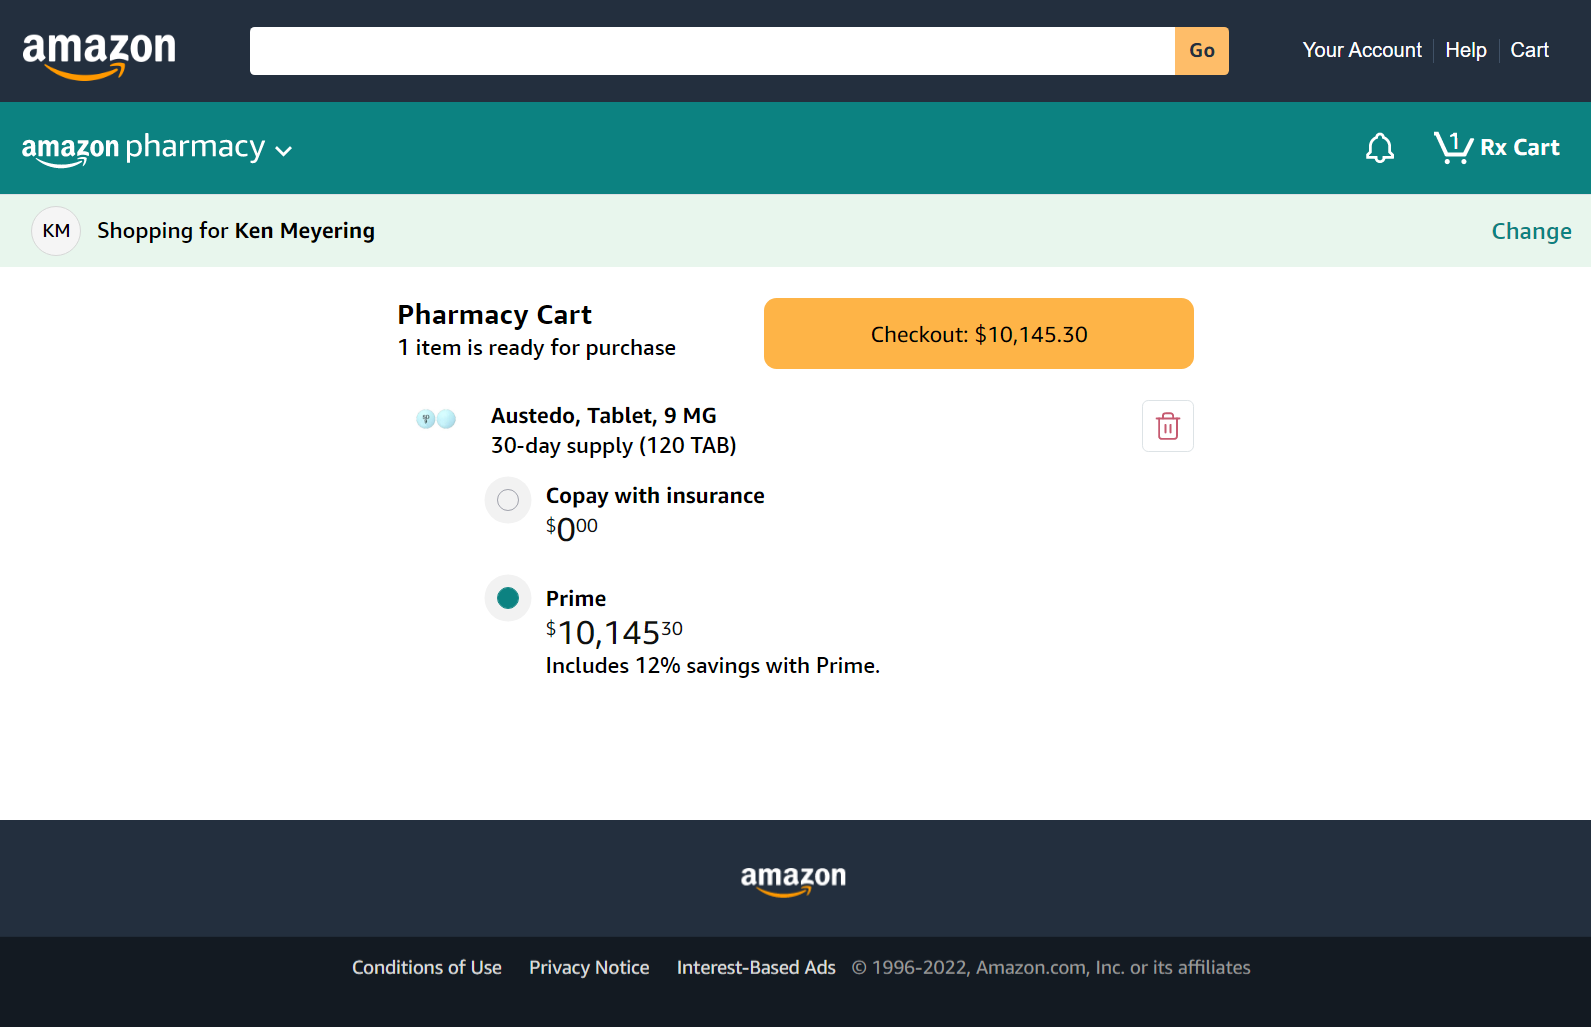

https://media.define.com/Kens-Austedo-Prescription-Price.jpg